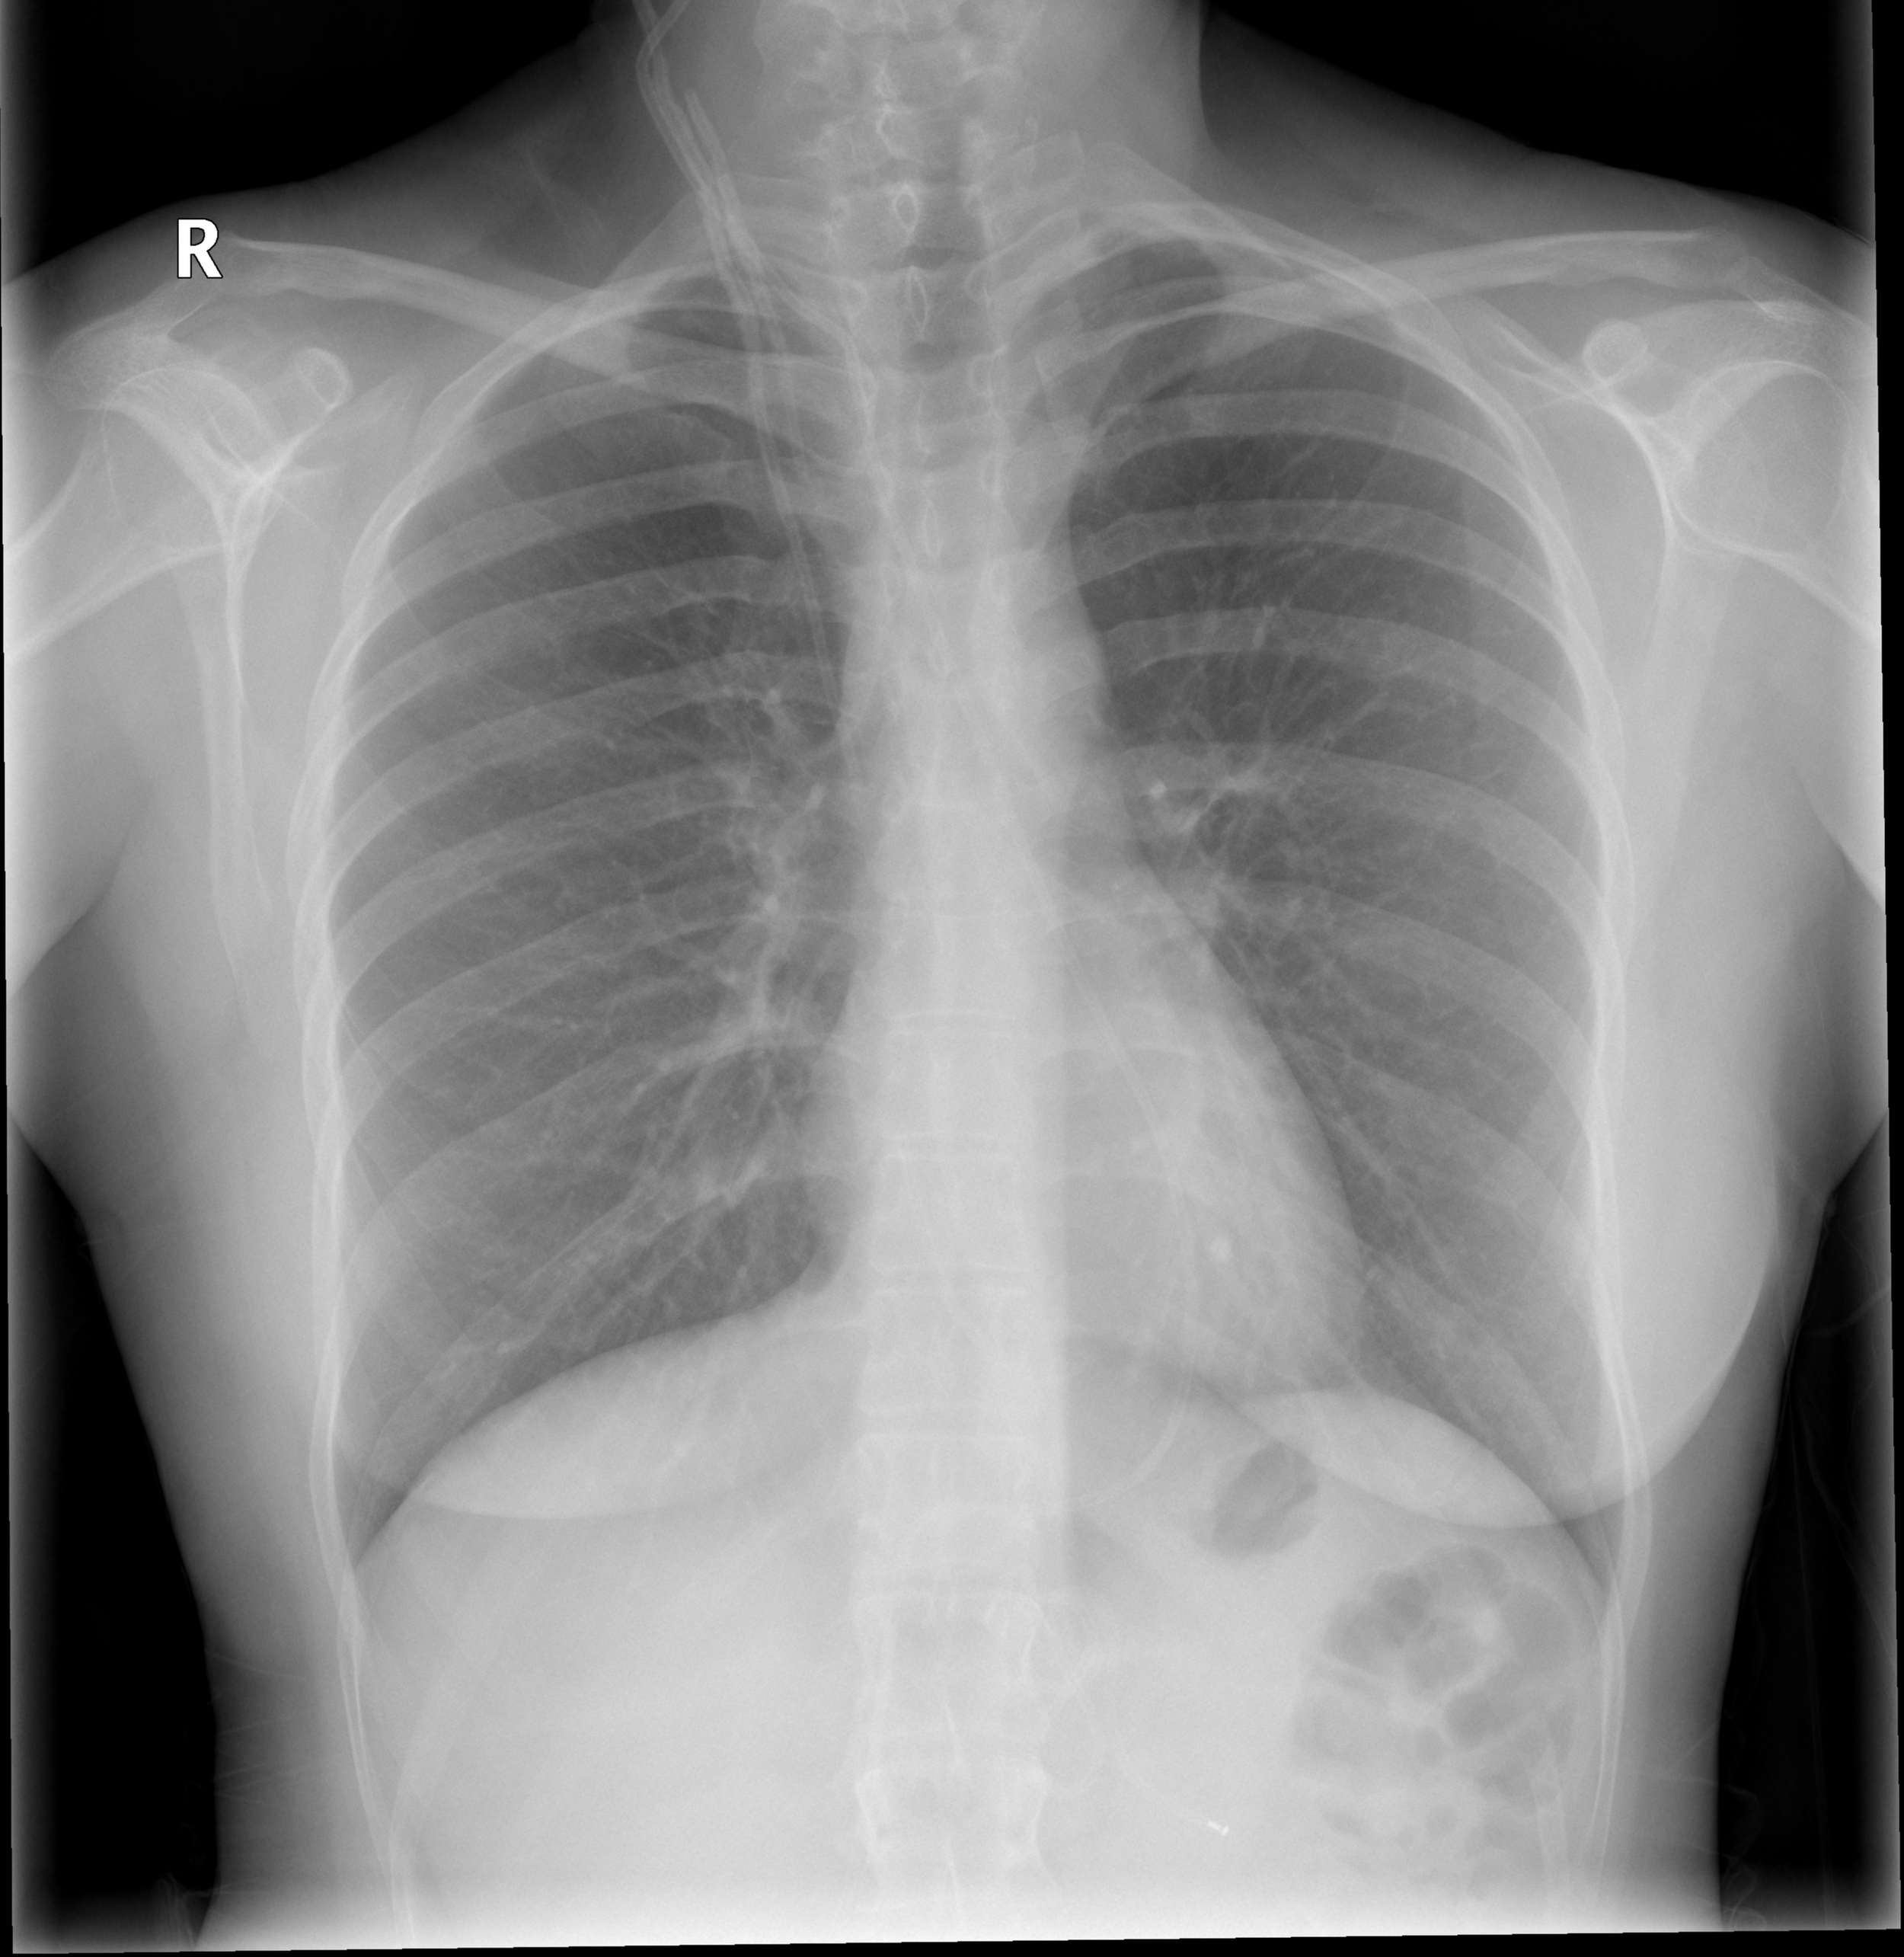

Broad infectious workup should be initiated. A normal leukocyte count on CBC does not exclude a shunt infection, which may be localized. Other sources of infection should be excluded with chest x-ray, urinalysis and a thorough skin exam. Blood cultures should be obtained and broad-spectrum antibiotics/antivirals initiated. Most shunt infections are from skin flora such as Staphylococcus epidermis, S. aureus, and gram-negative rods. Consultation with neurosurgery is essential as these patients need source control in addition to standard antimicrobial therapy for meningitis or encephalitis.